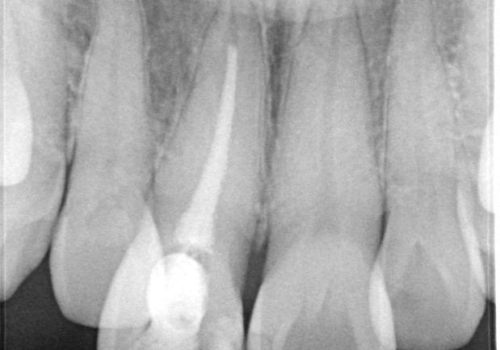

右上1は根管治療がされており、神経がないため歯自体も変色していること、詰め物の色も変色していることをふまえ、オールセラミッククラウン(スペシャル)による治療を行うことになりました。

根尖に病変はないこと、患者さんが根管治療は希望されなかったため、土台のやりかえからかぶせものまでを行っております。